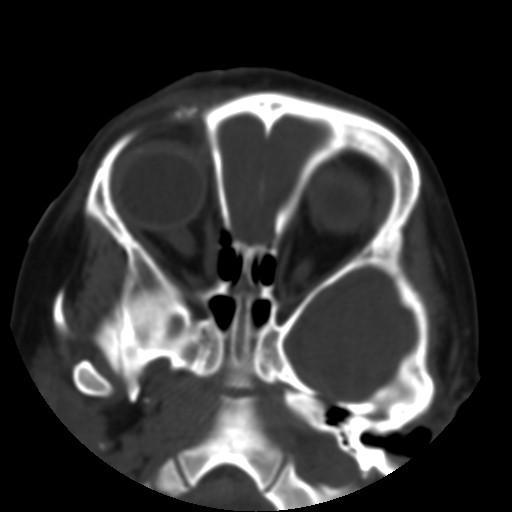

以下是引用深泽交通医院在2009-10-16 8:25:00的发言:[br]右眼环出血伴异物

以下是引用卜一在2009-10-16 15:01:00的发言:[br]右眼球挫裂伤伴异物!

以下是引用拾荒者在2009-10-17 18:38:00的发言:[br]鼻面部皮下积气,右侧睑缘及眼球壁高密度异物影,左侧眼球壁晶状体内侧缘处是圆形低密度影。低密度异物?应提请眼科医生注意。